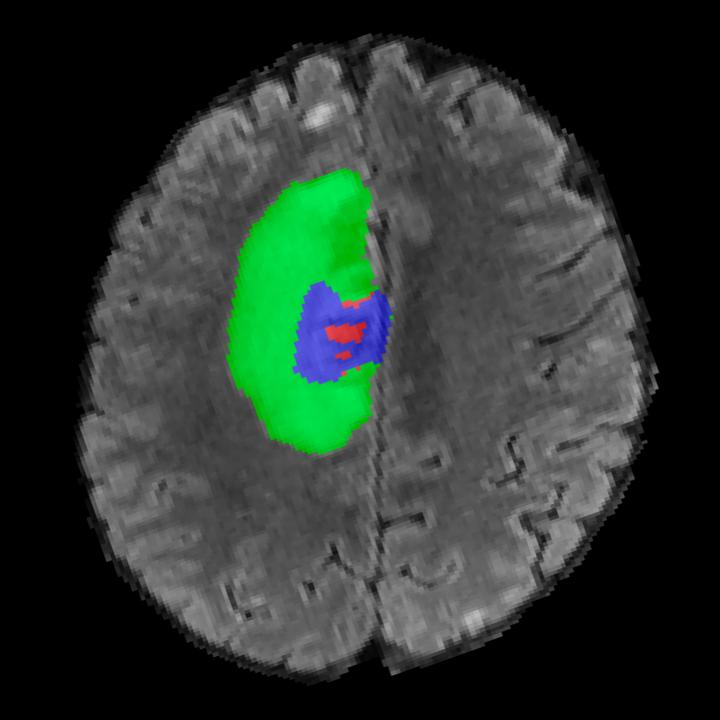

Tumour Information Preservation. For the brain tumor segmentation, we use a Swin UNETR model[27, 70], trained with random rotation, and intensity as data augmentation. In Figure 5, we highlight the tumor profiles of the generated MRIs compared to the ground truth tumour profile. In the test set with human ground-truth annotations (), the real MRI Dice score is 85.15 while the generated MRIs from a single slice have a dice score of 83.09. This shows how the generated MRIs indeed preserve the tumor information and can act as an affordable and informative pseudo-MRI, before conducting an actual costly MRI examination in hospitals.

B.4 Tumour Information Preservation

On the test set with human ground-truth annotations (), the brain volumes generated from single slice input preserve the volume of the different tumour components (paired t-test, for all 3 classes) (see Table 3). The real MRI Dice scores are put for reference to our generated MRIs. X-Diffusion outperforms baselines TPDM [36] and ScoreMRI [18] in tumour preservation (see Table 3 and Figure 12). We ran experiments comparing the tumour segmentation Dice Score varying X-Diffusion configurations. The multi-slice input X-Diffusion achieves a marginally better Dice Score than the single-slice input model (83.47 83.09). We also ran experiments with slice input used for volume reconstruction intersecting or not with tumour. We observe on average a drop of 6% Dice Score (see Table 3). Further away from the tumour the input slice for volume reconstruction is selected, and we observe a linear decrease in tumour segmentation Dice Score with the lowest value of 77.21 Dice Score (see Figure 15).